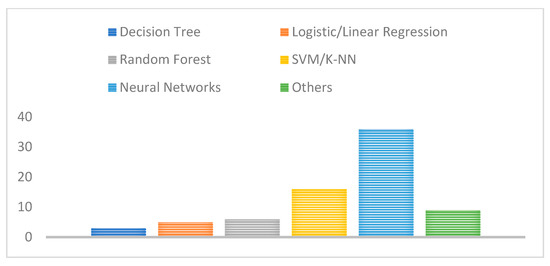

In addition, the majority of the adopted machine and deep learning techniques proposed in the literature were based on neural networks such as ANNs, CNNs, as well as typical machine learning methods including SVM and KNN as shown in Figure 11. This also shows the widespread and superior performance benefits of neural network technologies compared with traditional feature extraction and classification techniques where features are automatically extracted without any human intervention.

Figure 11.

Number of studies for each deep learning technique adopted.